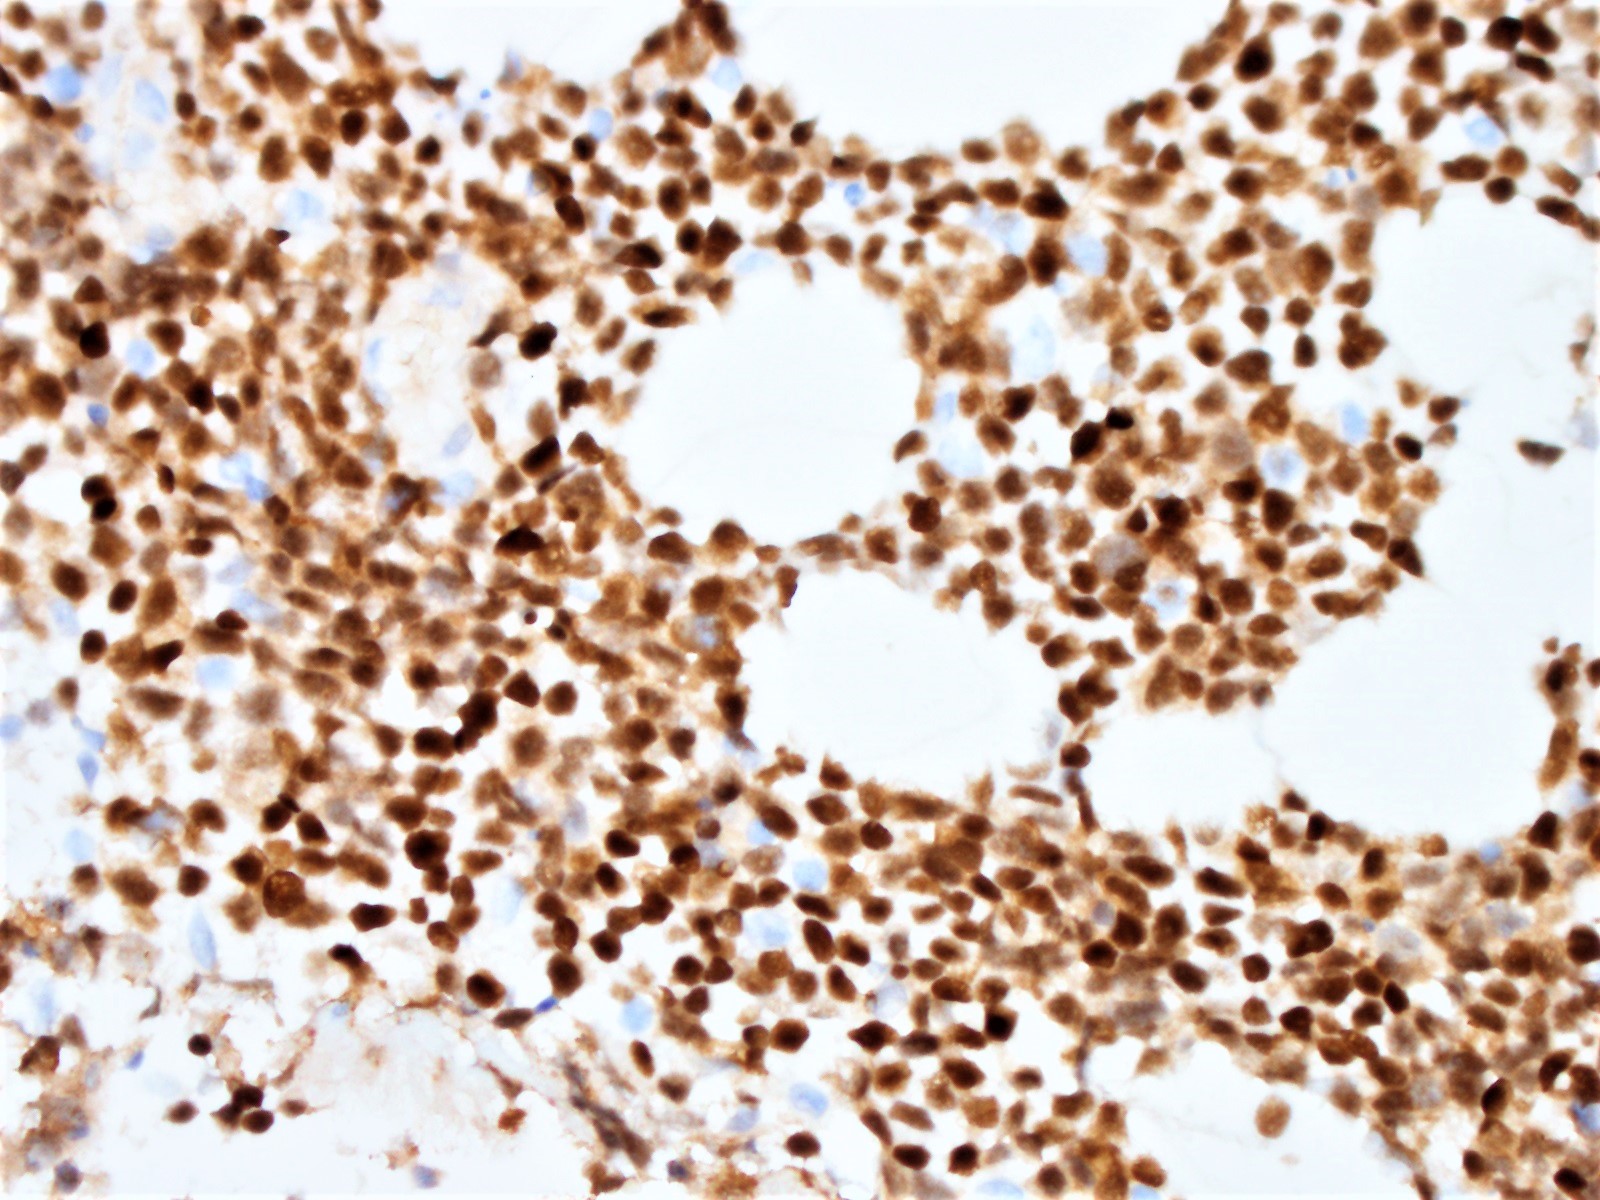

Microscopic (histologic) images

Positive stains

- Cyclin D1

- Ki67 count (J Hematop 2009;2:103)

- Note: Ki67 index is not sufficient to classify as blastoid or pleomorphic subtype

- Classical mantle cell lymphoma might also show high cell proliferation (Blood 2008;111:2385)

- p53 in subset; intense expression correlates with TP53 gene mutation